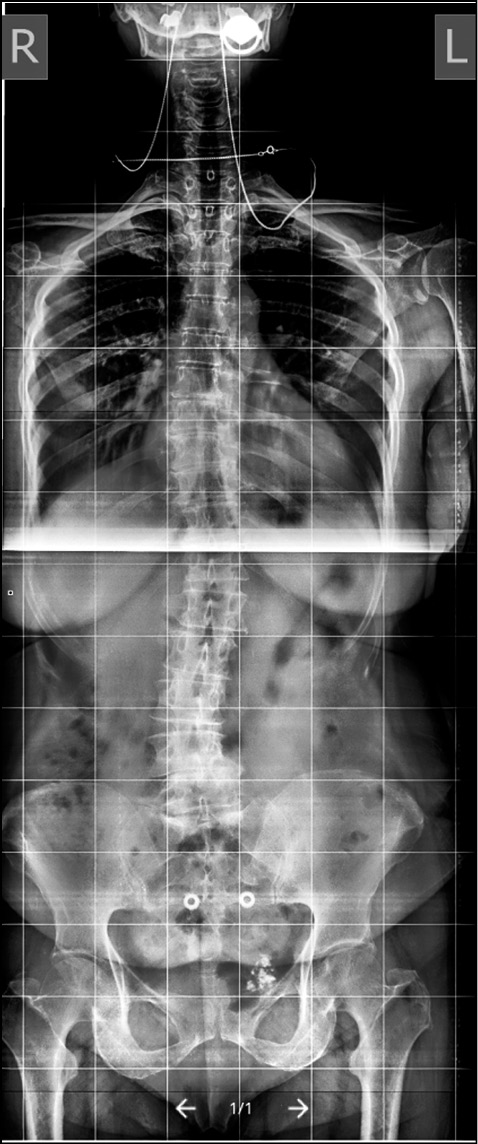

При поясничном ADS с большой степенью кривизны и подвывихе апикального ТП высокой степени всегда требуется корригирующая деформация. Как правило, в данную группу входят пациенты с углом деформации >45°, подвывихом >2 мм и отсутствием передних остеофитов в зоне операции с корректным фронтальным и сагиттальным балансом (рис. 2).

Рис. 2. Продолжительная фиксация и коррекция при ADS (фото М.Ю. Докиша). / Fig. 2. Extended fixation and correction in ADS (photo by M.Y. Dokish).

Передний спондилодез посредством трансфораминального межтелового (transforaminal lumbar interbody fusion, TLIF) или экстремально-латерального межтелового (extreme lateral interbody fusion XLIF) доступа может быть важным дополнением к стабилизации на уровне поясничного отдела позвоночника у данных лиц, особенно если планируется введение винтов в крестец и таз [28]. Снижение болевого синдрома и удачно выполненный спондилодез для коррекции ADS и восстановления LL и сагиттального баланса является ключевым в хирургическом лечении. Обычно при помощи задней инструментальной фиксации можно добиться коррекции деформации ADS, однако проблематично восстановить LL [60, 61], для чего требуется проведение переднего релиза межпозвонковых структур с поддержкой передней опорной колонны. Восстановление сагиттального баланса достигается за счет опорной способности передней колонны или выполнения остеотомий позвонков.

В 2020 г. А.А. Денисов и соавт. [62] подтвердили, что применение лордозирующих кейджей с углами 20–30° значительно увеличивает сегментарный лордоз и LL. Степень полученной коррекции сегментарного лордоза и LL была идентична прогнозируемым результатам (рис. 4, 5).

Рис. 4. Спондилограмма пациента с ADS до операции (из [62]). / Fig. 4. Spondylography of an ADS patient's spine before the surgery.